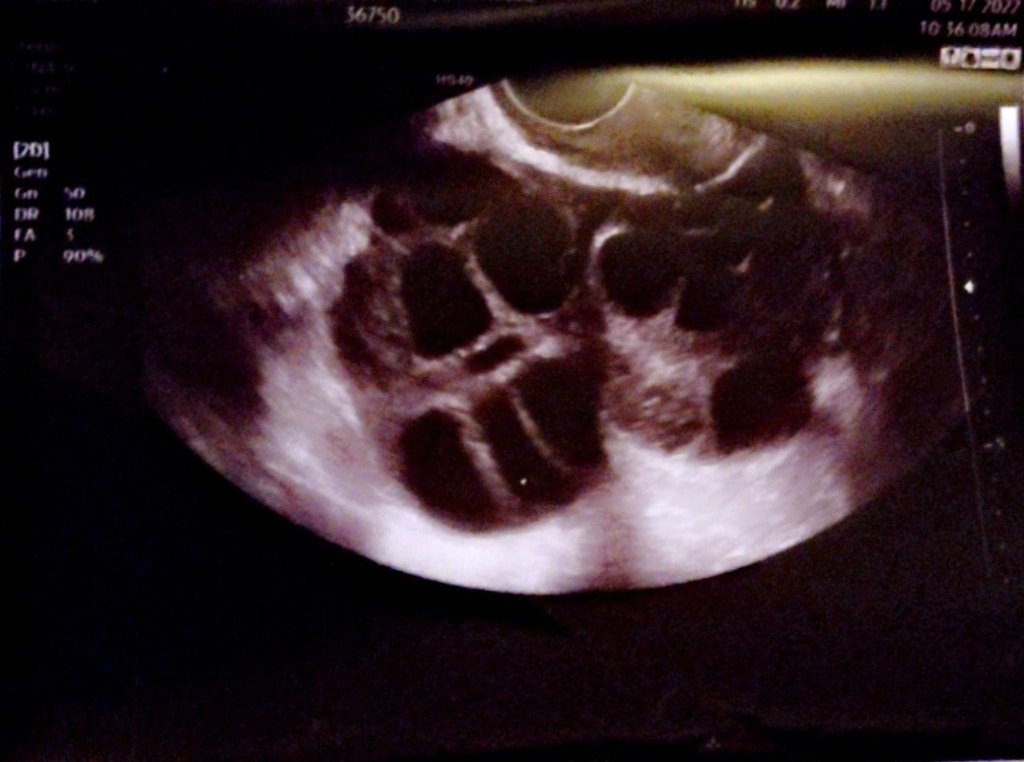

I started my IVF injections on May 6th 2022. These medications were to help stimulate my ovaries and encourage follicle growth for my egg retrieval. I did my trigger shot on May 17th. The injections weren’t too bad, I did have to give them to myself in the abdomen everyday which was interesting. My Egg retrieval was on May 18th. I had 60+ mature follicles WHICH IS AMAZING. AND HURT LIKE HELL.(my ovaries were swollen and touching!!)

My very swollen ovaries touching. The sacs you see are follicles. Follicles are small fluid filled sacs they carry developing eggs.